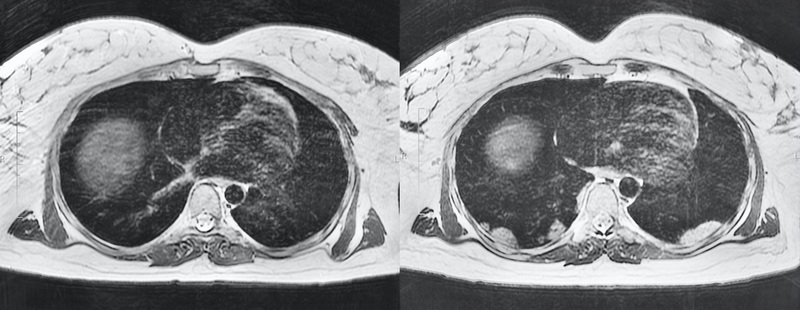

Chest MRI of a pregnant woman with COVID-19 pneumonia

This paper presents a clinical case of a 39-year-old pregnant woman with respiratory signs of the novel coronavirus Covid-19 infection. Chest MRI showed bilateral lesions in basal segments. The PCR test was positive. A lung condition was assessed without loss of significant diagnostic information. Besides that, the absence of exposure to ionizing radiation allowed to avoid a high loading dose on the patient and the fetus. This case reveals potential opportunities of MRI in the diagnosis of pulmonary pathology without exposure to ionizing radiation, especially in patient risk groups (children, pregnant women, etc.).